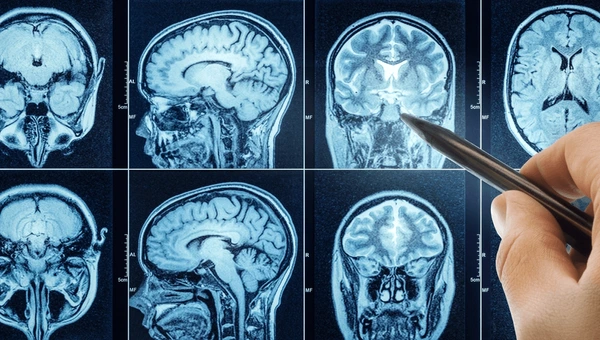

Shunting for hydrocephalus involves implanting a ventriculoperitoneal shunt to drain excess cerebrospinal fluid; neuroendoscopy is commonly used for third ventriculostomy as a shunt-free alternative. Brain tumor resection uses intraoperative MRI, neuronavigation, and fluorescence guidance to safely remove malignancies like medulloblastomas or gliomas. Open cranial vault remodeling or endoscopic assistance are utilized in the treatment of craniosynostosis to release fused skull sutures. For spina bifida repair, there are two options: postnatal myelomeningocele closure with duraplasty or prenatal fetal surgery. Two forms of epilepsy surgery include hemispherotomy and laser interstitial thermal therapy. Chiari malformation decompression and spinal tethered cord release round out their procedural repertoire; all procedures are performed with neuromonitoring to protect neurological function. Contact us now because Dr. Gaurav Varshney is one of the Best Doctor For Pediatric Neurosurgery in Aligarh.